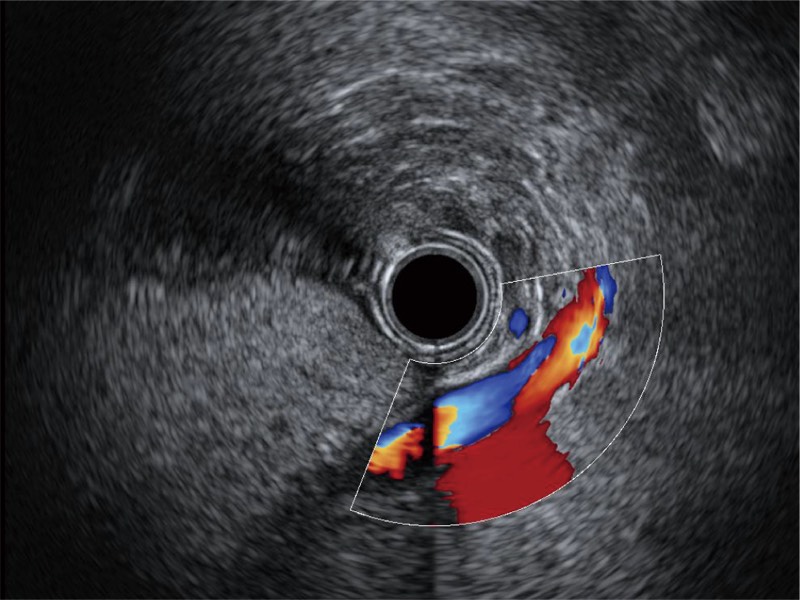

清晰显示胆总管及周围血管分布

可人为将灰阶图像转变成彩色的显示方式,增强人眼对于不同回声强度的敏感度,主观上增加了图像分辨率